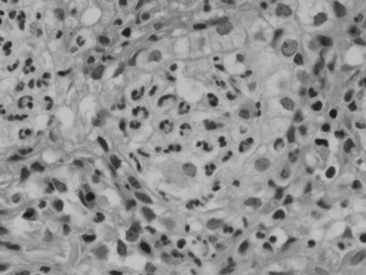

Viral agents are frequently implicated or suspected but rarely identified by the usual serologic, histopathologic, and virus isolation methods. The advent of more sensitive and specific techniques, such as in situ PCR and monoclonal antibody IHC, may partially resolve the current diagnostic challenge. Most recently, a novel gamma-EHV, EHV type 5 (EHV-5), has been found associated with a nodular form of interstitial pneumonia of horses characterized by pulmonary interstitial fibrosis, suggesting that these rather unusual cases may have an underlying infectious cause.420 This disease has been termed equine multinodular pulmonary fibrosis by the authors describing the pathology of the disease. Horses affected generally have a history of fever, cough, and weight loss, accompanied by exercise intolerance and finally respiratory distress. They can be acutely affected or have a more chronic progressive problem. Typical radiographs reveal multiple discreet to coalescing nodular densities overlying a diffuse interstitial pattern (Figs. 31-31 and 31-32). Histologic appearance is diagnostic of this disease (Figs. 31-33 and 31-34). EHV-5 has been identified in both BALF and lung biopsy samples from affected patients by both PCR assay and IHC.

image

Fig. 31-32 Cut section of lung from horse with equine multinodular pulmonary fibrosis. Note large areas of apparent fibrosis within the pulmonary parenchyma.

Courtesy Dr. Perry Habecker, University of Pennsylvania, New Bolton Center, Kennett Square, Penn.

Fig. 31-33 Postmortem histopathologic specimen from a horse with severe equine multinodular pulmonary fibrosis. This is the histologic appearance of one of the fibrotic nodules. The alveoli are constricted within dense neoformed fibrotic tissue. Alveoli have an abnormal cuboidal epithelium (type 2 pneumocytes), and the lumen contains macrophages, sloughed epithelial cells, and neutrophils. Denser and diffuse fibrotic areas present.

Courtesy Dr. Fabio Del Piero, University of Pennsylvania, New Bolton Center, Kennett Square, Penn.

Fig. 31-34 Postmortem histopathologic specimen from a horse with severe equine multinodular pulmonary fibrosis. Note abnormal alveolar cuboidal epithelium, and within the lumen neutrophils and intranuclear amphophilic viral inclusion with chromatic margination within a sloughed epithelial cell or perhaps a macrophage.